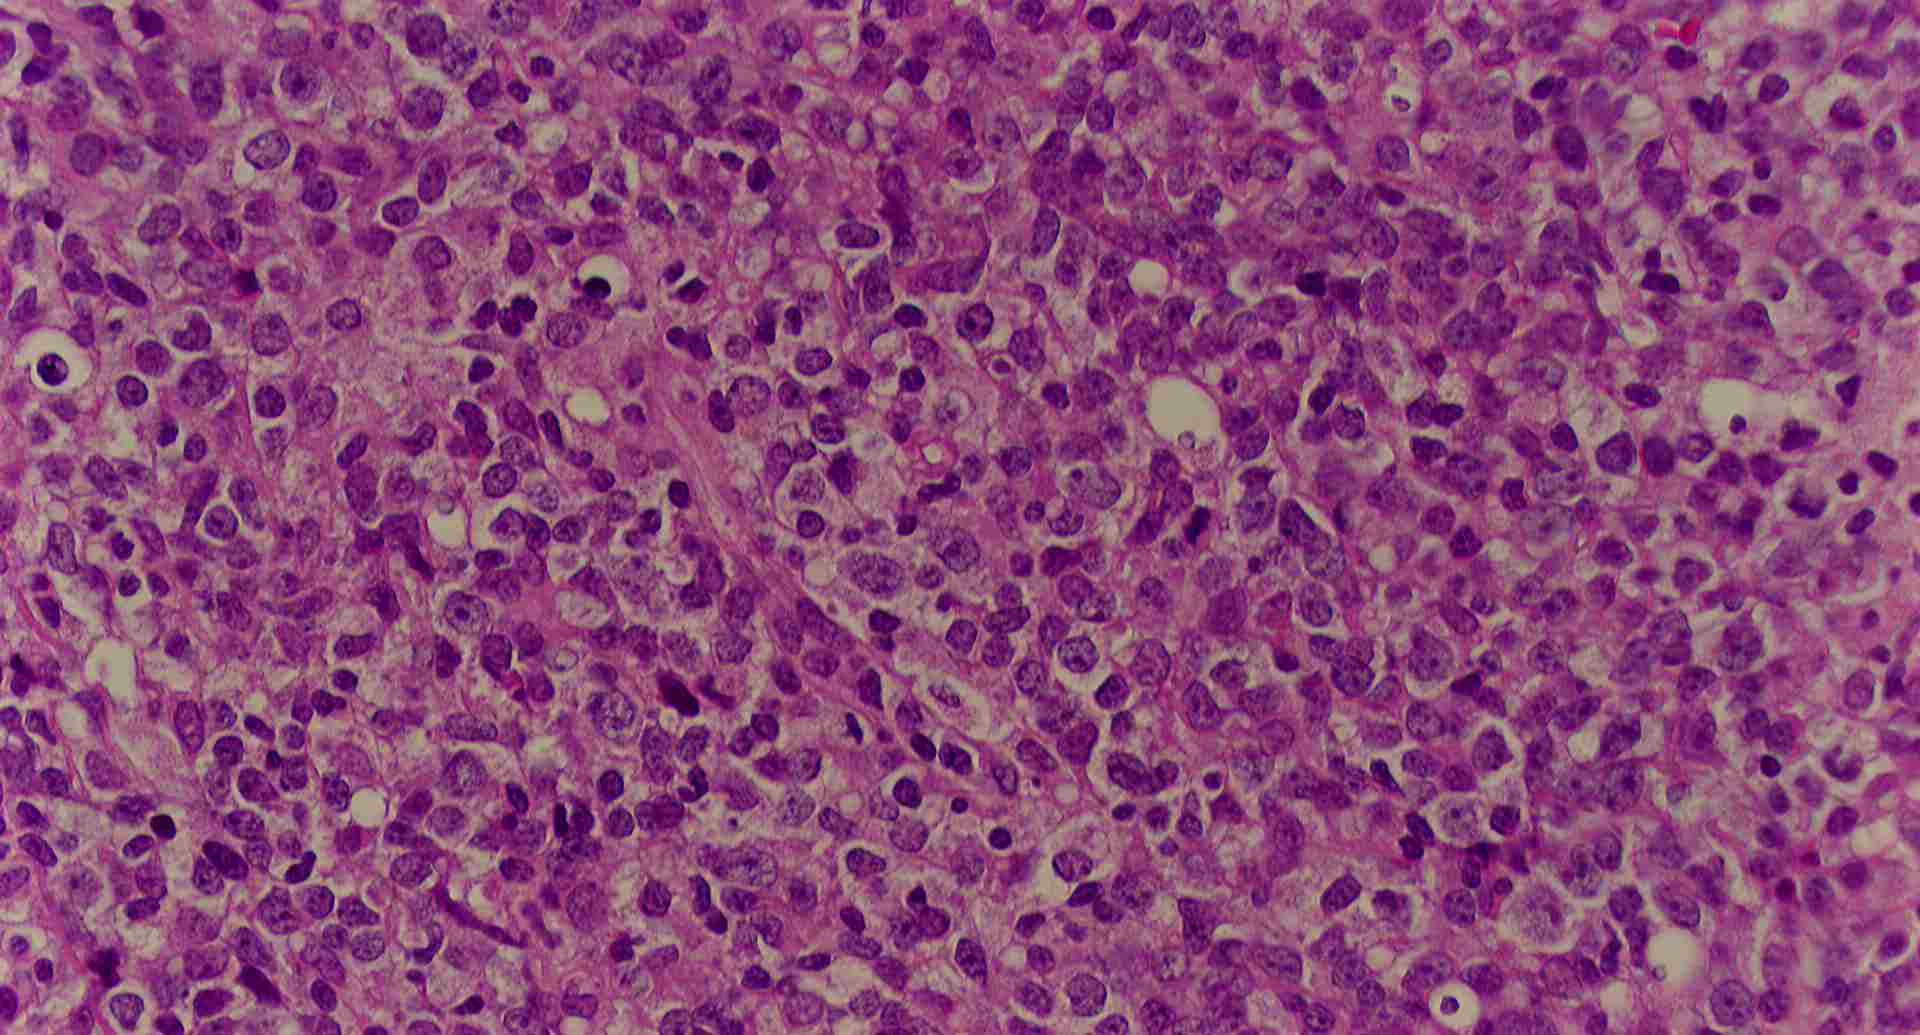

標本1

標本1の説明